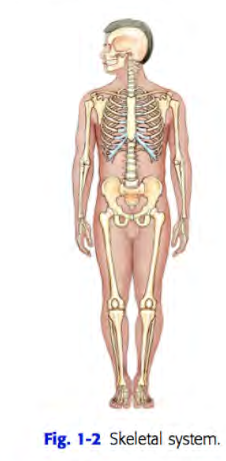

Human body 10 systems

(l) skeletal

Skeletal system

includes the 206 separate bones of the body and their associated cartilages and joints